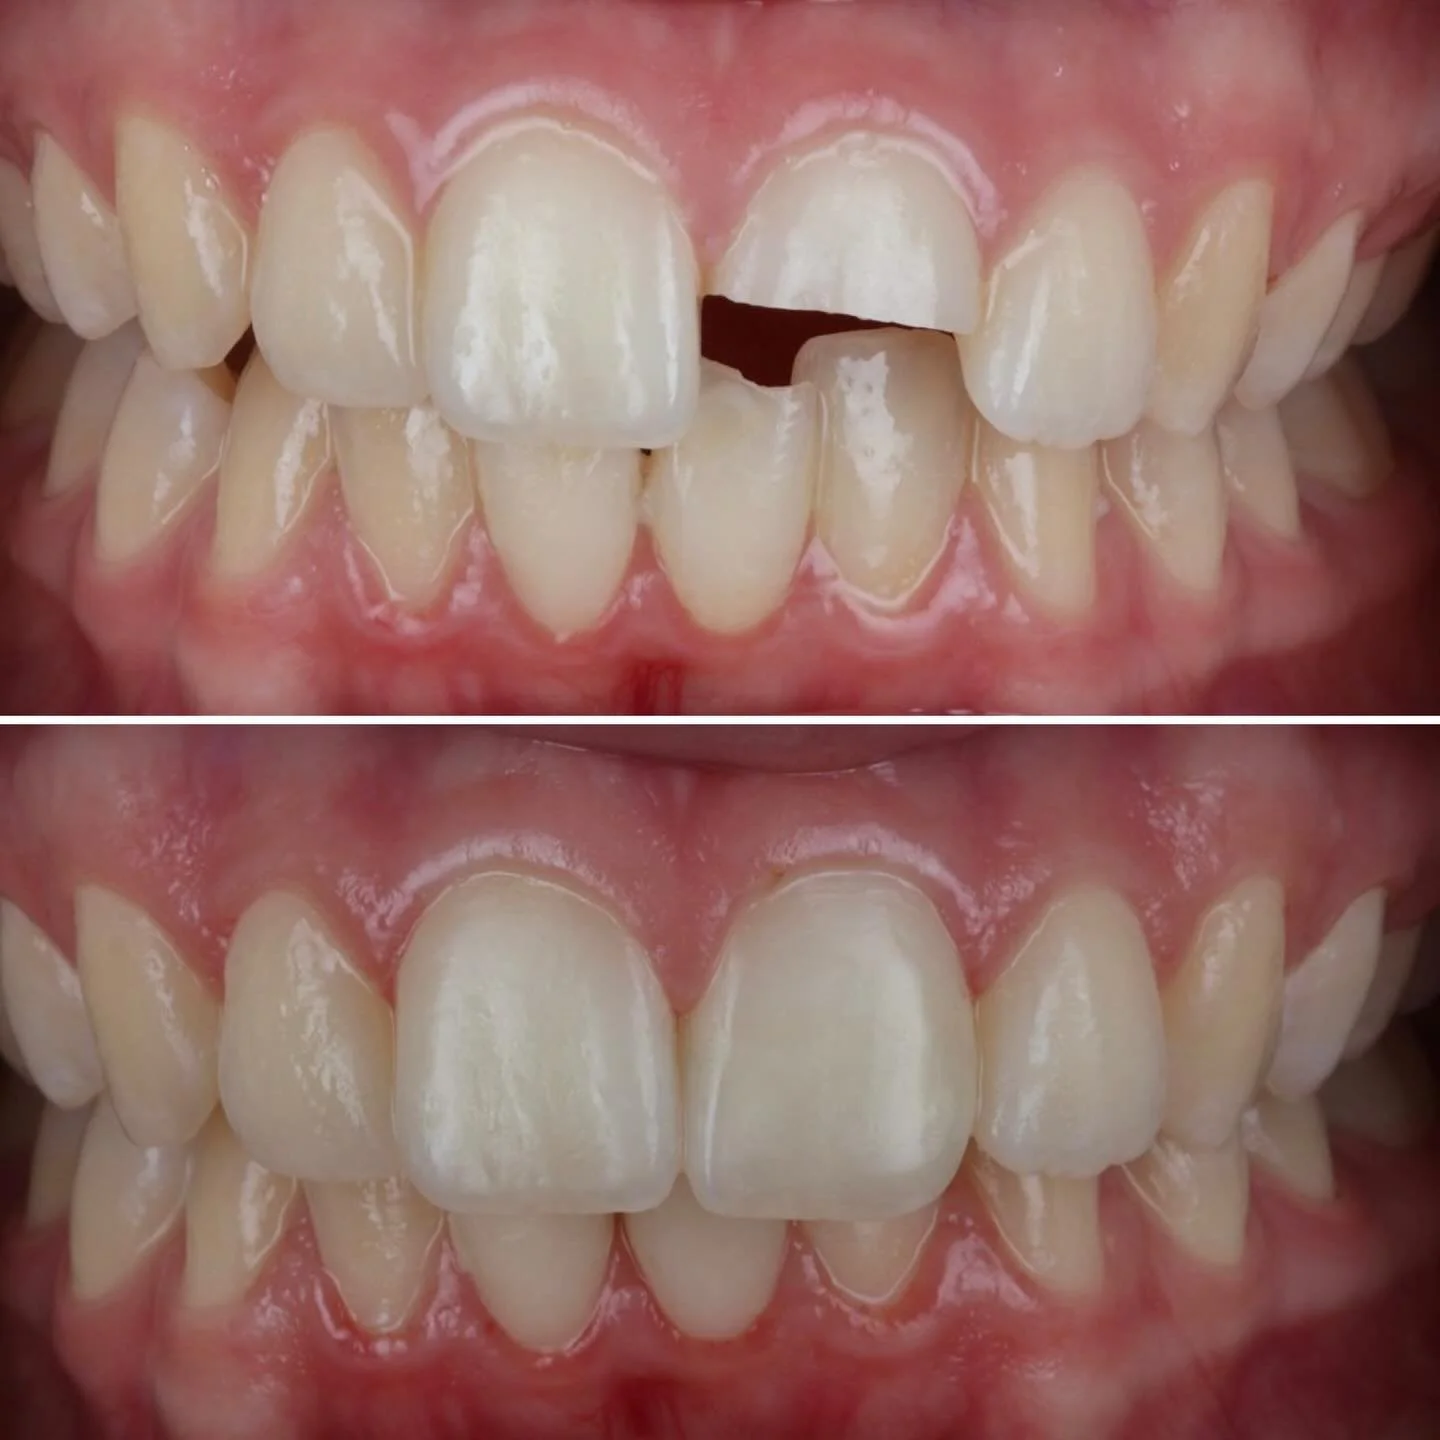

We are an award winning, local family run practice providing advanced implant, cosmetic and family dentistry

We donβt treat teeth, we treat people - you are unique, with individual needs and we have the solutions.